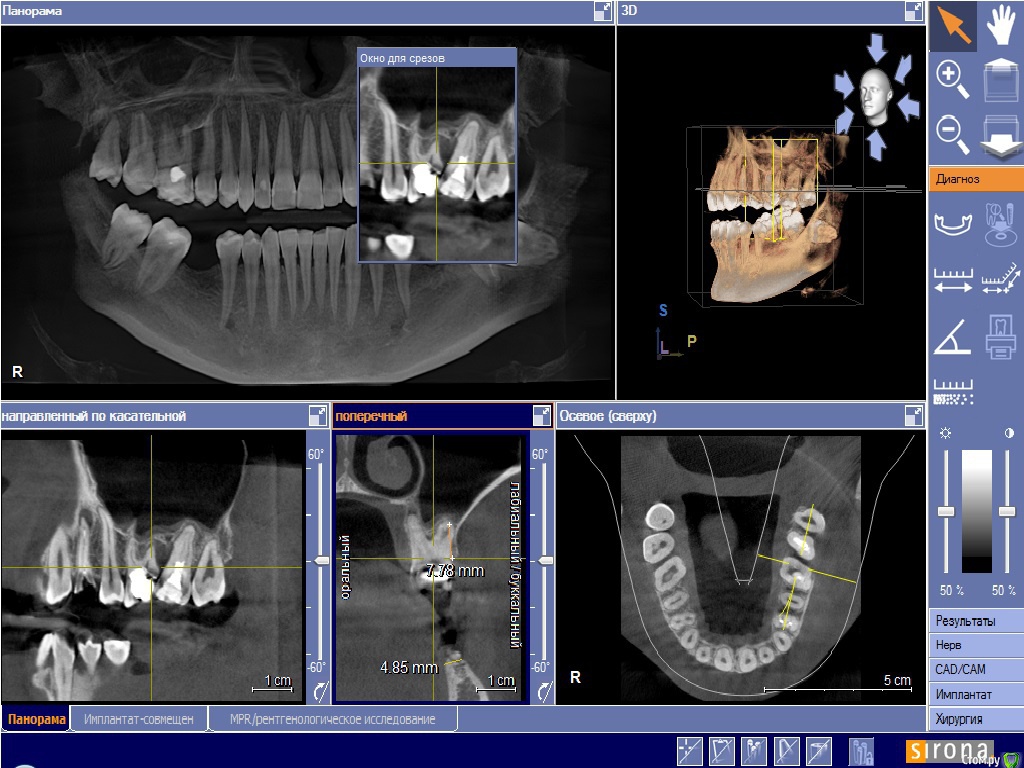

Doctor Vlad Опубликовано 31 января, 2016 Поделиться Опубликовано 31 января, 2016 здравствуйте!зуб 24 и корешок 36 удалены ранее 2 мес назад, слева: и верх и низ молярная группа сохранению не подлежит! 26 ниже уровня кости разрушен... карман между 26 и 27 до верхушки. 7 подвижна слегка. пациент хочет имплант в 24 первоначально. удалять жевательную группу пока не хочет но протезировать будет на имплантах.мои мысли: поставить 24 да пусть он там приживается месяца 3. тем временем удалить верх 26 27 кюретаж засыпать БИООС для сохранения высоты кости мембрана зашить. 28 как стенка дефекта пусть постоит) по заживлению верха удаление низ 37 38. через 3 месяца импланты в области 26 и 36.. чз месяца 3 одновременно запротезировать 24 26 36 и ввести в функцию.не стоит отдельно перегружать 24, лучше уговорить на одномоментную нагрузку? сильно перегрузиться правая сторона за время отсутствия левой? ваше мнение? альтернативные варианты.. предложения)? Ссылка на комментарий